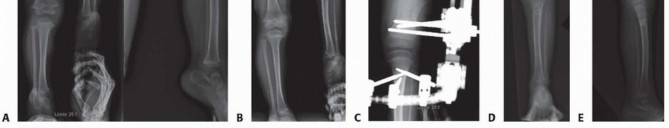

Illustration 3 for Treatment for Congenital Femoral Deficiency: What You Need to Know Illustration 4 for Treatment for Congenital Femoral Deficiency: What You Need to Know Illustration 5 for Treatment for Congenital Femoral Deficiency: What You Need to Know Illustration 6 for Treatment for Congenital Femoral Deficiency: What You Need to Know FIG 2 • A. Paley type 1b CFD (subtrochanteric type) shown by illustration, radiograph, and MRI. Note the nonossified subtrochanteric cartilage B. Paley type 1b CFD (neck type) shown by illustration, radiograph, and MRI. Note the nonossified neck. *

Because of the correction of the abduction contracture and the opening wedge of the Dega, it is not possible to close the apophysis. The apophysis is pulled up and the level marked with a pen. The crest is then resected using a saw until the medial and lateral apophysis can be repaired without excessive tension ( TECH FIG 3C,D ). This is called the abductor slide technique . The TFL is then sutured to the rectus femoris ( TECH FIG 3E ). The incision is closed in layers. A suction drain is used and is left in place until the drainage stops (<10 mL per 24 hours), which can take several days. Prophylactic antibiotics are administered intravenously until the drain is removed. Illustration 30 for Treatment for Congenital Femoral Deficiency: What You Need to Know Illustration 31 for Treatment for Congenital Femoral Deficiency: What You Need to Know Illustration 32 for Treatment for Congenital Femoral Deficiency: What You Need to Know TECH FIG 4 • A,B. CFD Paley type 1b with delayed ossification of femoral neck. C. Superhip procedure at age 2 years including insertion of BMP in femoral neck. D. The neck is fully ossified by age 3 years. E,F. First lengthening is performed at age 4 years with Smith & Nephew Modular Rail System external fixator with articulation across the knee joint. G. Eight centimeters of lengthening is achieved. H. Removal of external fixator with Rush rodding of bone to prevent fracture. A spica cast is applied with the hip in full extension, neutral abduction, and neutral rotation. The knee is splinted in full extension. The cast is bivalve to allow for swelling. One week after surgery, the cast is made removable and gentle flexion and extension ROM of the hip and knee started. TECH FIGS 4 and 5 are two case examples of superhip procedures. *

Illustration 33 for Treatment for Congenital Femoral Deficiency: What You Need to Know Illustration 34 for Treatment for Congenital Femoral Deficiency: What You Need to Know TECH FIG 5 • A. Two-year-old girl with CFD Paley type 1b with delayed ossification and severe angulation of the subtrochanteric level of the femur. B. The deformity is fully corrected, and the femur is healed after the superhip surgery. C. Lengthening of the femur was performed at age 4 years. D,E. X-rays after lengthening of the femur 7 cm and insertion of Rush rod. 1. # Superknee Procedure